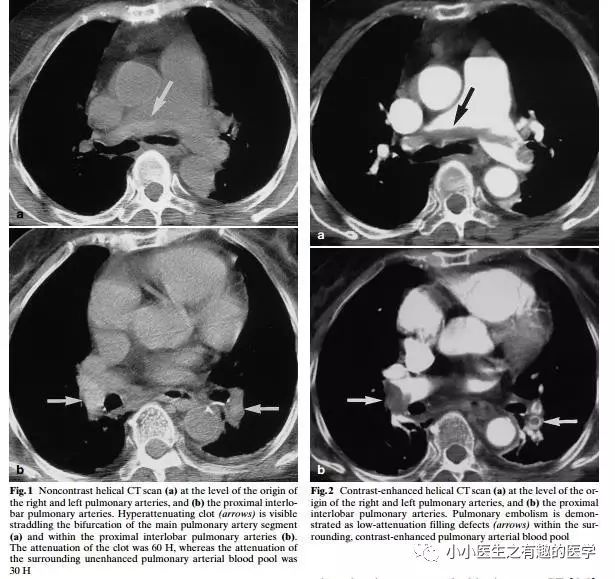

作者单位:Department of Radiology, Thoracic Imaging Section, San Francisco General Hospital(旧金山总医院)。

如图,高密度影的那一条。

不怕,有增强CT证实。

上面图片的英文原版

1.Gotway M B, Webb W R. Acute pulmonary embolism: visualization of high attenuation clot in the pulmonary artery on noncontrast helical chest CT[J]. Emergency Radiology, 2000, 7(2):117-119.